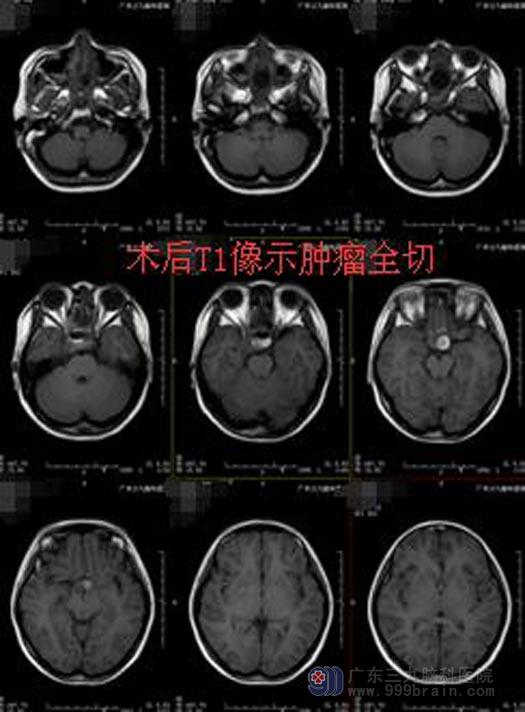

鲁明主任主刀在全麻内镜下行经鼻碟鞍区垂体瘤切除术,术中再次导航定位,镜下见灰白色肿瘤组织,质软,镜下全切肿瘤。术后小何神志清醒,没有出现尿崩、电解质紊乱、脑脊液漏等并发症,右眼视力视野也在慢慢改善。

小姑娘最开心的是她心爱的头发一根没少。